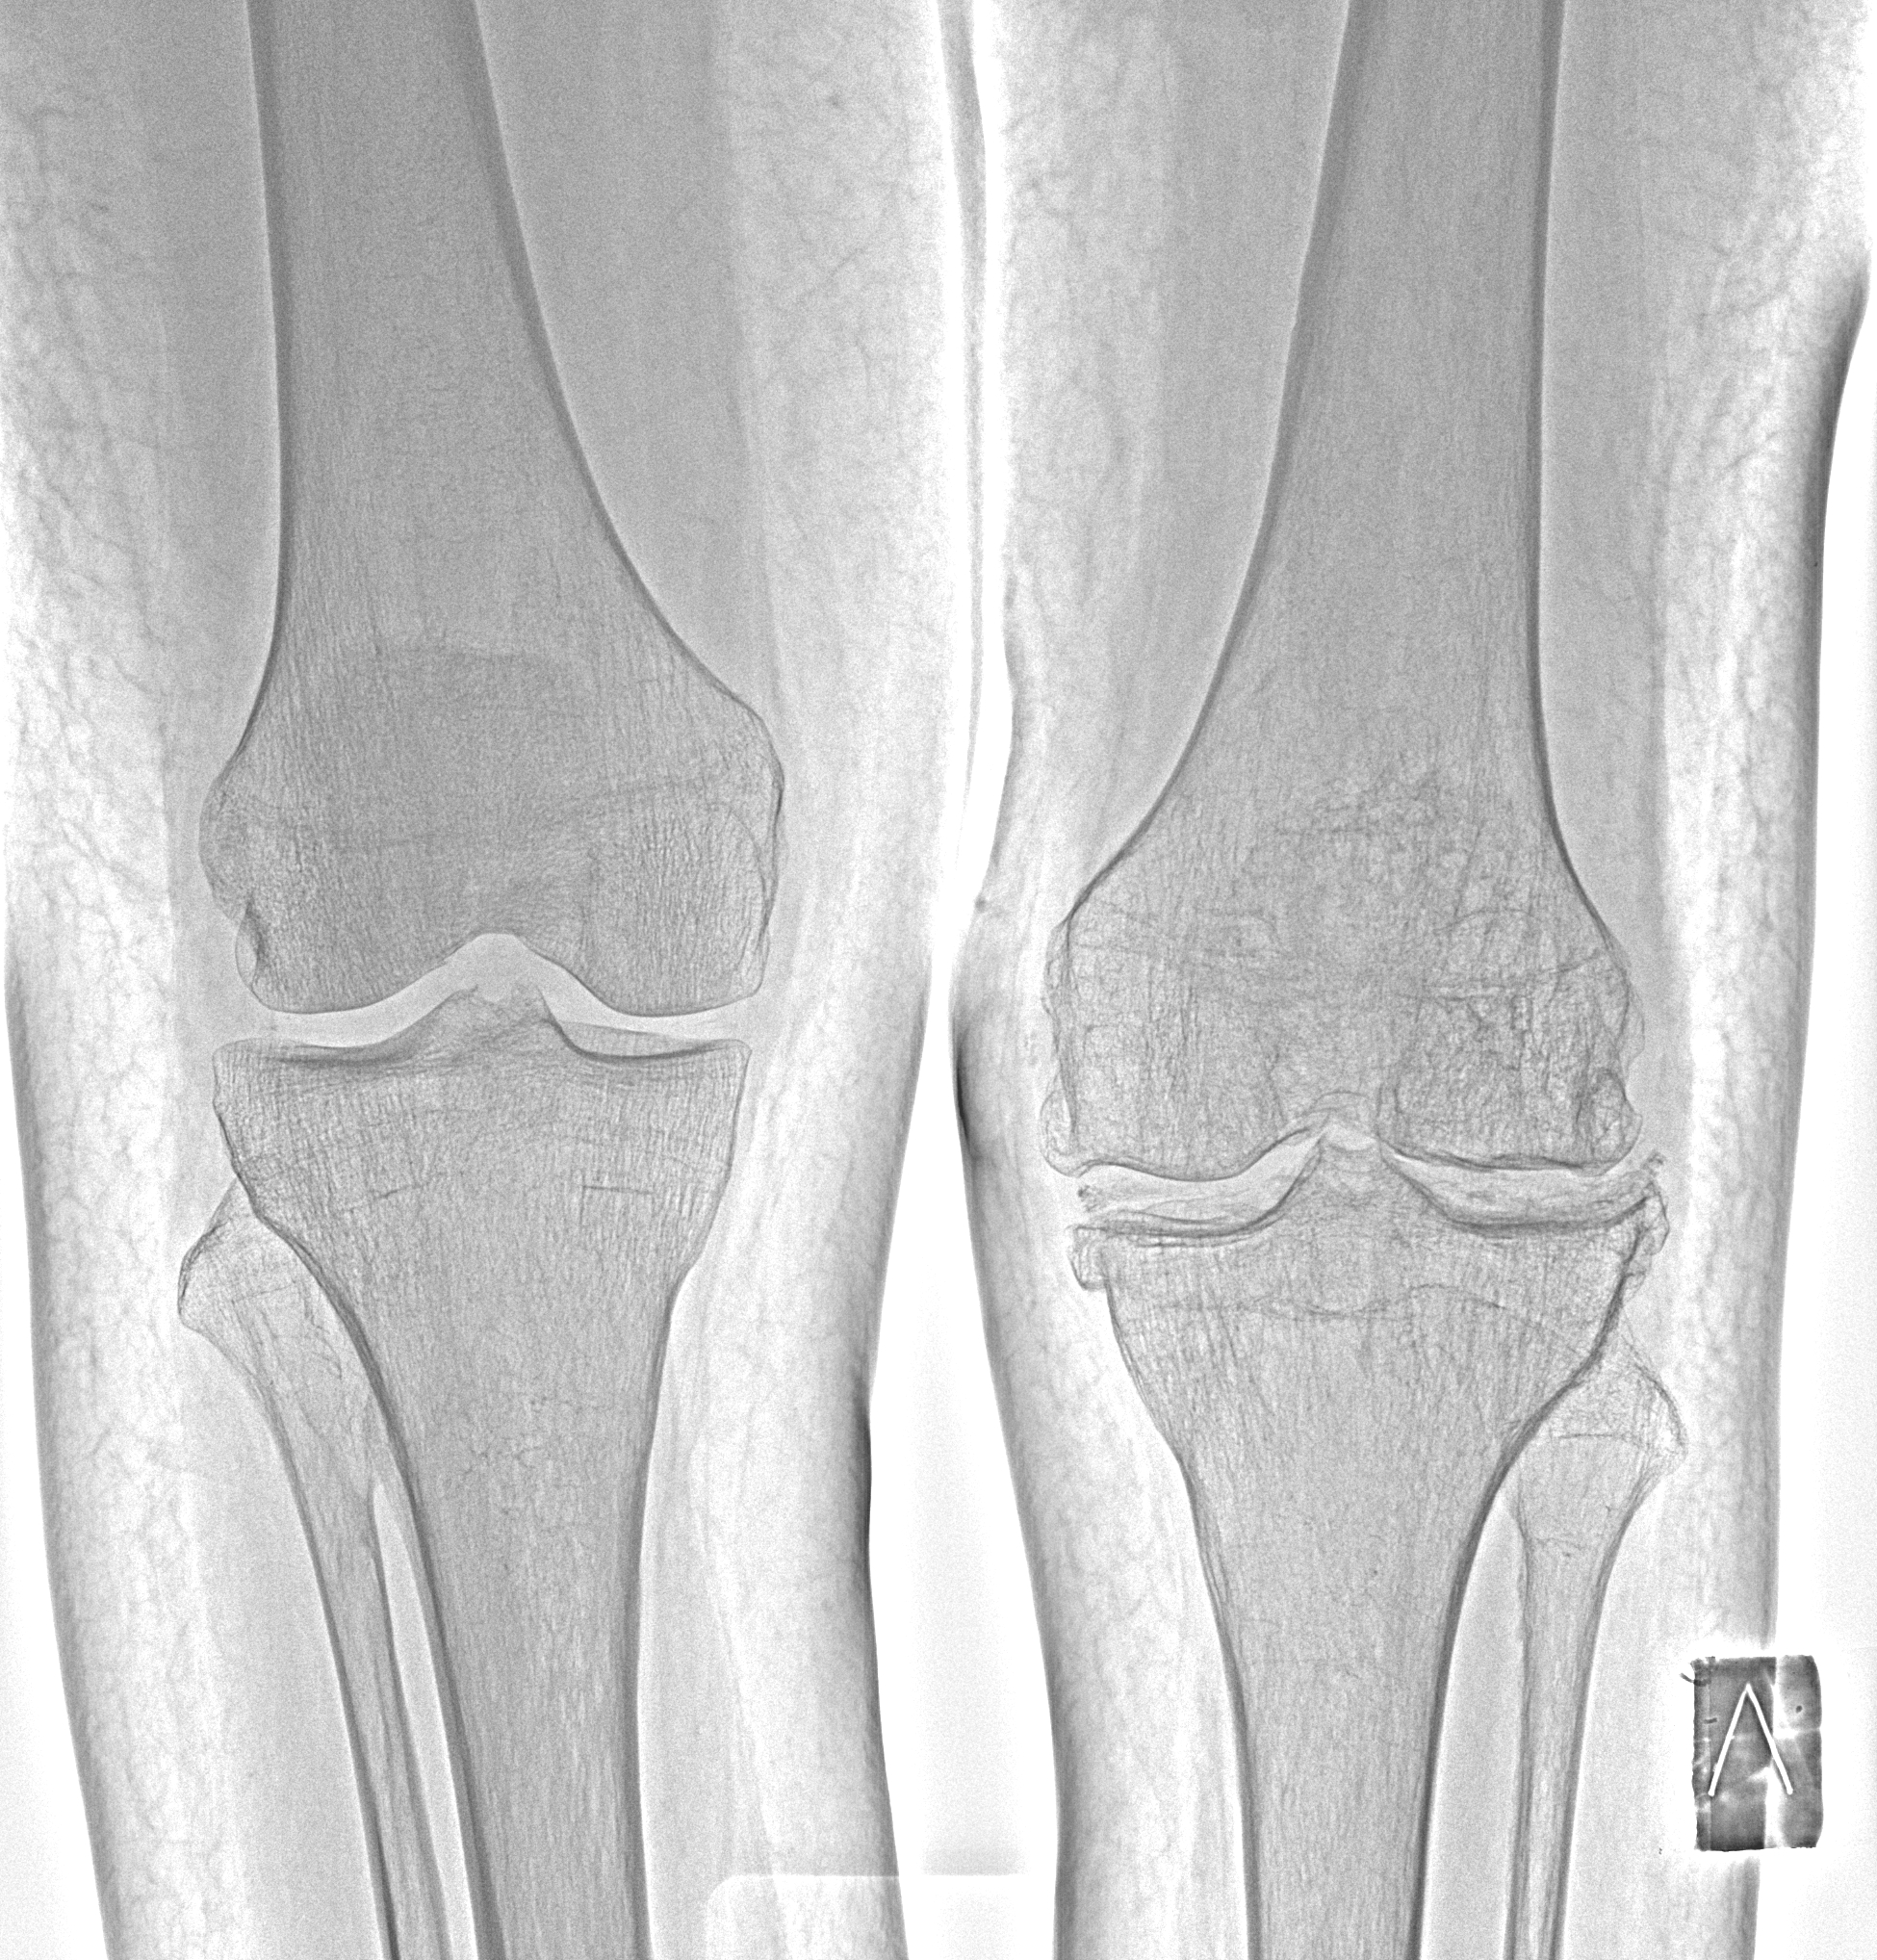

Сросшийся перелом мыщелка